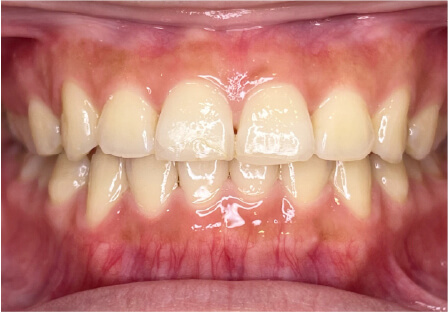

叢生の症例

11歳

/

女性

相談内容

上の前歯の歯並びが気になる(マイオスマイルからの移行)

カウンセリング・診断結果

インビザライン、拡大入れながらスペースを作成、下Eは出てきたら削りながら進める

治療内容・方法

全額アライナー矯正 クリアコレクト

術後の経過・現在の様子

クリアライナー使用

治療のリスク

痛み・歯根吸収・歯肉退縮・虫歯・後戻り

費用・治療期間

移行料金220,000円、月々16,500円、1年1ヶ月+myo2年3ヶ月

トレーニングなど